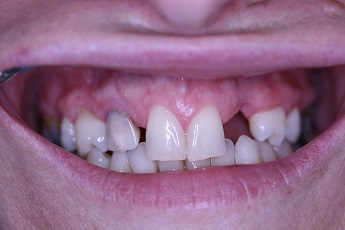

![]() |

Foto 27, 28: Stav před a po kompletním ošetření rekonstrukci ortodontické vady fixním můstkem.